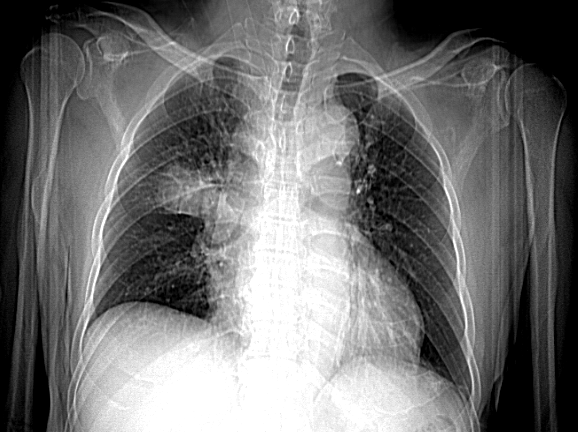

image (1).png

1년 전 흉부 엑스레이 VS 1년 후 흉부 엑스레이

폐암은 암 사망률 1위의 질환으로 많은 이들이 두려워한다. 어떤 질환이든 빨리 발견하는 것이 예후에 중요하다. 폐암 역시 그렇다. 우리는 건강검진 목적으로 해마다 찍은 흉부 엑스레이를 찍지만, 폐암을 조기 진단하는 검사법이 아니다.

2019년 12월에 보고된 한 연구에 의하면 폐암의 증상이 있는 사람이 흉부 엑스레이로 폐암을 진단받을 확률은 80%에 불과했다. 나머지 20%는 흉부 엑스레이에서 폐암을 찾지 못했다. 5명 중 1명은 폐암 증상이 있어도 엑스레이로 폐암을 진단받지 못했다. 이들은 폐암의 증상이 있는 경우였으므로, 증상이 없는 초기 폐암을 엑스레이로 진단하는 것은 극히 드문 일이다.

폐암은 빨리 자라는 암으로 폐암의 부피가 두 배로 커지는 데 걸리는 기간은 98일 (중앙값 기준)이다. 짧게는 한 달 만에 두배로 커지기도 한다. (소세포 폐암 30일, 편평 상피세포암 100일, 선암 180일) 이런 이유로 폐암을 진단받은 사람의 경우 65%에서 1년 이내 선별 검사에서 엑스레이를 찍었을 때 암이 없었다는 연구 결과도 있다.

폐암의 병변 특성상 흉부 엑스레이에 드러나지 않을 수 있다. 특히 암의 직경이 1CM 미만의 암의 경우 누락될 가능성이 높다. 만약 폐암이 상엽에 있거나 갈비뼈, 폐혈관, 심장과 같이 해부학적으로 겹치는 부위에 있다면 엑스레이로 진단이 어렵다. 그밖에 미숙련자와 영상 판독 실력이 부족한 경우도 폐암 진단의 누락 원인이 되기도 한다.